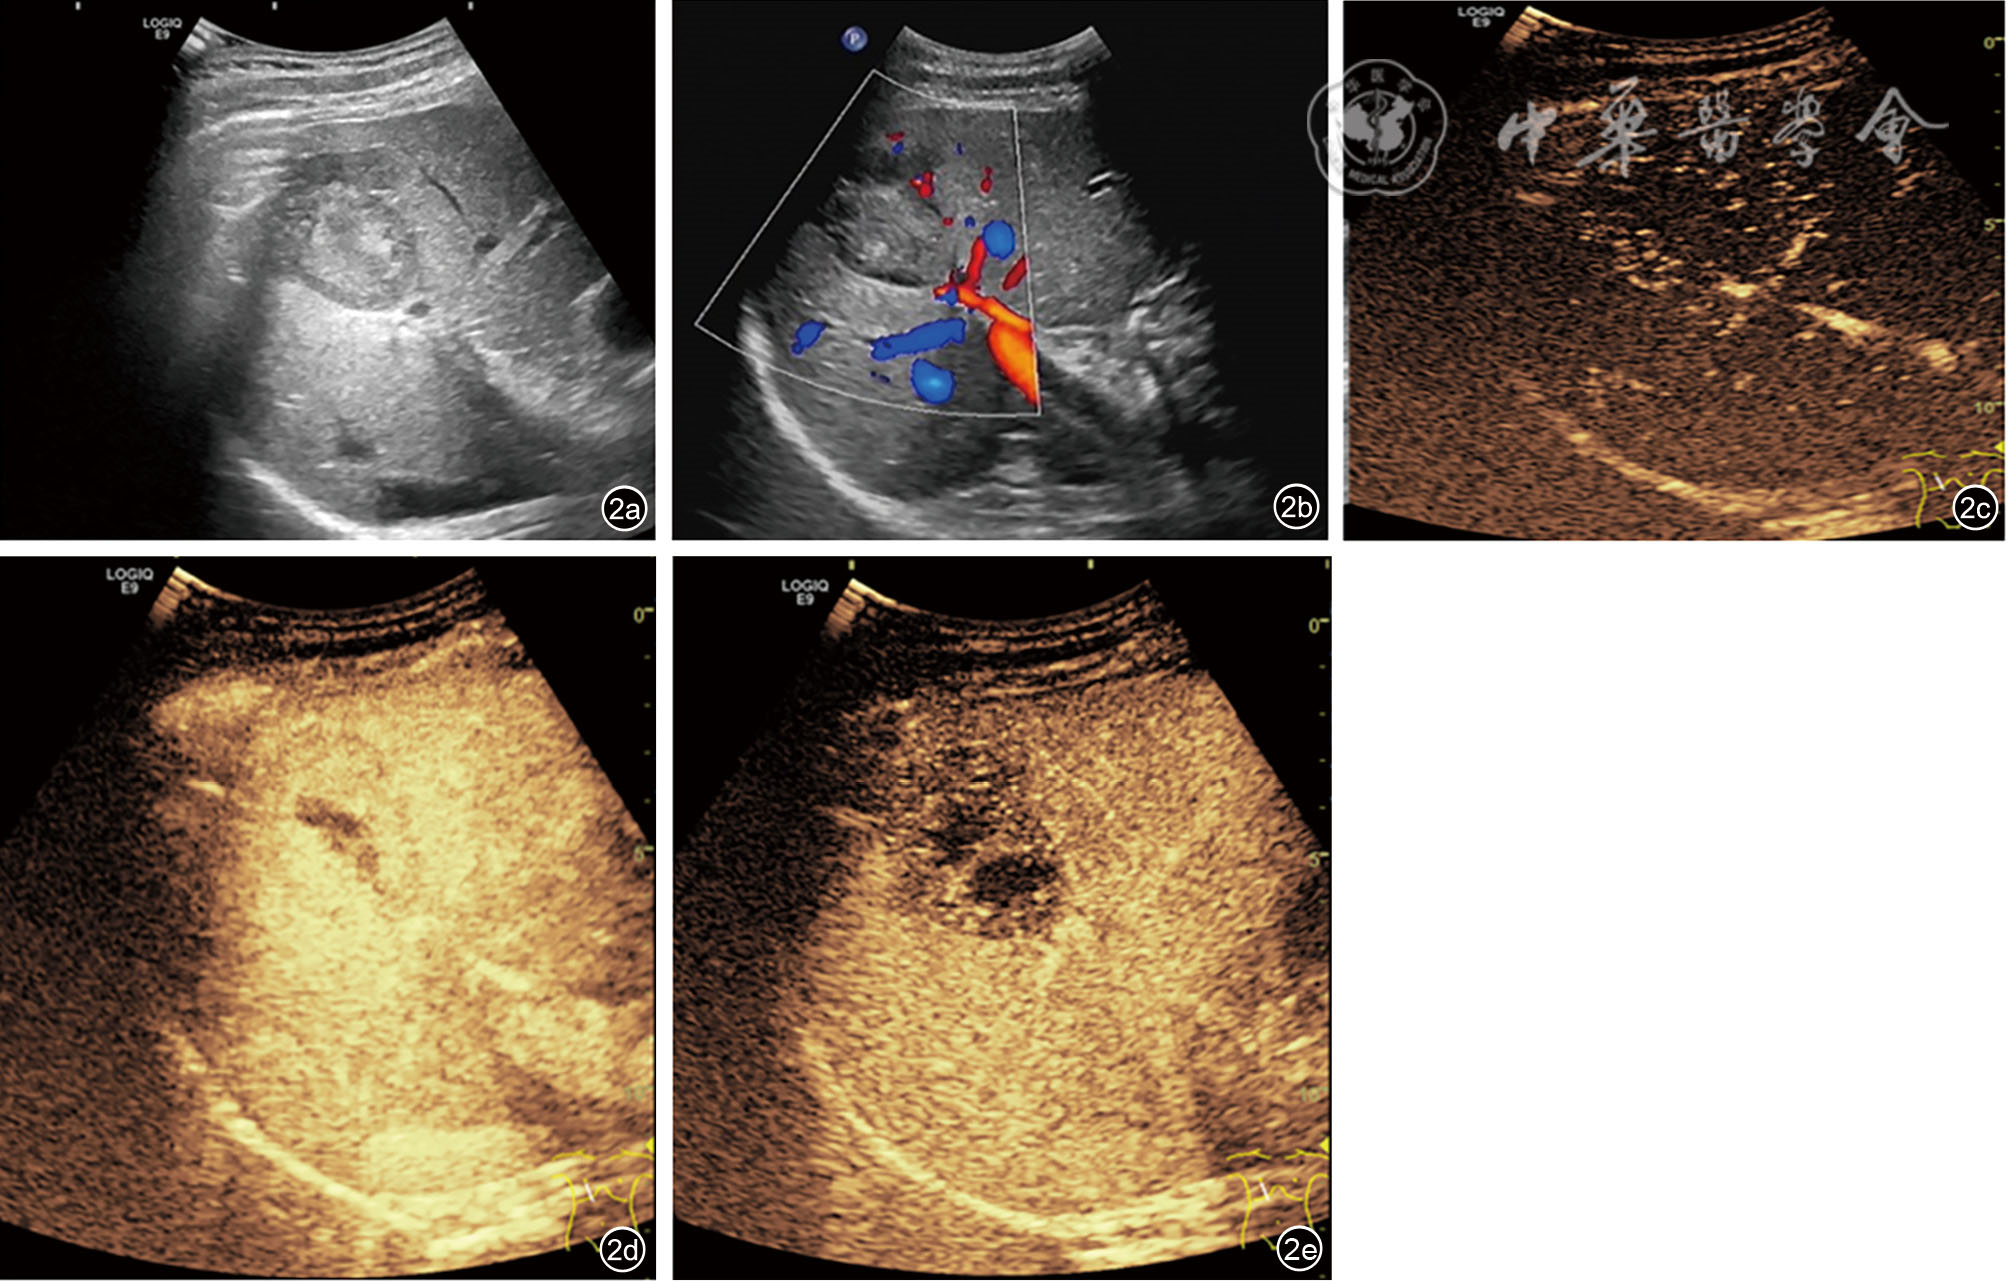

患者男性,42岁,右下腹酸胀疼痛3个月,无发热、寒战、周身黄染等其他症状,无肝炎病史。深圳市人民医院门诊CT检查发现肝右叶一类圆形低密度影,边界欠清楚,大小约4.5 cm×4.2 cm,增强扫描呈填充式强化,内壁欠光整,病灶内见小片状无增强区,动脉期病变周围见异常灌注(图1)。CT提示:肝右叶占位,考虑肝脓肿可能性大,肿瘤性病变待排查。实验室检查:直接胆红素浓度为8.5 μmol/L,总胆红素浓度为30.7 μmol/L,丙氨酸氨基转移酶40.1 U/L,碱性磷酸酶125 U/L,其余指标均在正常范围内。中性粒细胞比值、中性粒细胞绝对值在正常范围内,肿瘤标志物癌胚抗原、甲胎蛋白、糖类抗原199均阴性。入院行抗感染治疗1周后复查超声:肝右前、后叶交界处可见一大小约4.9 cm×4.6 cm实质性团块,形状欠规则,内部为不均质低回声,边界尚清楚,无声晕,彩色多普勒血流成像见团块周边较丰富血流信号,内部见少量血流信号。超声造影:经肘静脉团注造影剂2.4 ml,14 s肿块周边实质呈快速不均匀增强;24 s达峰值,中央可见无增强区,范围2.6 cm×1.5 cm;于门脉期早于周边实质开始消退,延迟期进一步消退(图2);结合超声造影提示:考虑肝细胞癌可能,肝脓肿待排查。进一步行磁共振造影检查:肝右叶见大小4.9 cm×3.5 cm类圆形长T1稍长T2信号影,弥散明显受限,中央见小片状长T1短T2区域,中央区域弥散未见受限,增强扫描病灶各期呈环形强化,中央未见明显强化,肝胆期未见明显造影剂摄取(图3),诊断:考虑肝脓肿,纤维板层样肝癌待排查。此后1周内多次复查腹部超声,均提示肝占位病变无明显变化,临床排除肝脓肿可能,考虑肝细胞癌可能性大。遂行机器人辅助腔镜下肝S8段切除术。常规病理:肿瘤大小4.0 cm×4.0 cm×3.5 cm,与周围肝组织界限尚清楚,在大量淋巴细胞、浆细胞、组织细胞及多核巨细胞的背景下,见梭形滤泡树突样或纤维母细胞样细胞呈条束状分布,核空泡状、核仁明显,可见多灶性坏死;免疫组织化学检测结果显示肿瘤细胞CD21(+)、CD23(+)、CD35(+)、SSTR2(+)、SMA(-)、CD3(-)、CD20(-)、CD138(浆细胞+)、Ki-67(20%+)、IgG4/IgG(<40%);原位杂交结果:EB病毒(Epstein-Barr virus,EBV)壳抗原IgA抗体阳性[EBV脱核RNA(Epstein-Barr virus enucleated RNA,EBER)+]。最终病理诊断为EBV阳性炎性滤泡树突细胞肉瘤(EBV+ inflammatory follicular dentritic cell sarcoma,EBV+IFDCS)。术后未进行放化疗,随访16个月未见肿瘤复发及转移。

图2 肝病灶彩色多普勒超声及超声造影图像。图a:肝内见一不均质低回声团块;图b:彩色多普勒显示周边较丰富血流信号,内部少量血流信号;图c:注射造影剂后14 s肿块周边呈快速不均匀增强;图d:门脉早期开始消退;图e:延迟期进一步消退